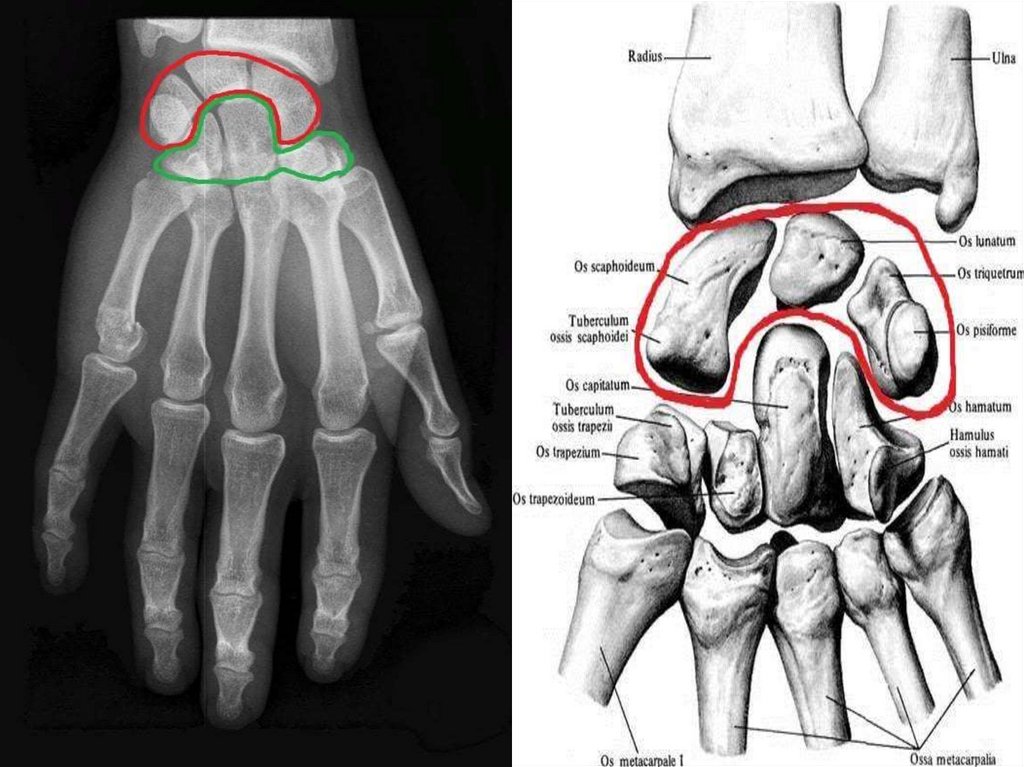

кінця – конусоподібний горбок і трапецієподібна лінія.

7.

Грудинний кінець закінчується грудинною суглобовою поверхнею

для з’єднання з ключичною вирізкою грудини, а надплечовий

кінець закінчується надплечовою суглобовою поверхнею для

з’єднання з надплечовим відростком лопатки.

Надплечовий (акроміальний)

кінець – масивніший та

з’єднується з грудиною.

Ключиця з’єднує в/к зі скелетом

тулуба, укріпляє положення

лопатки, окрім того утримує

плечовий суглоб на деякому

віддаленні від грудної клітки.

8.

Орієнтування ключиці в просторі:

Плоский кінець (надплечовий, акроміальний) спрямувати

латерально, а масивніший (грудинний) – медіально, горбок на кістці

спрямувати вниз.

Тіло ключиці вигнуте таким чином, що медіальна частина його,

ближча до грудини, випукла допереду, а латеральна – дозаду.

Основні анатомічні утвори ключиці:

1. Грудинний кінець –

extremitas sternalis

2. Тіло ключиці – corpus

claviculae

3. Надплечовий

(акроміальний) кінець –

extremitas acromialis

4. Конусоподібний горбок

(слід прикріплення зв’язок)

– tuberculum conoideum

9.

10.

Лопатка – scapula

Розміщується на задній поверхні грудної клітки, трикутної форми.

Парна плоска кістка, яка має:

1) Поверхні – реброву (передню) і задню;

2) Краї – верхній, медіальний і латеральний;

3) Кути – верхній, нижній, латеральний;

4) Ямки – підлопаточну, надостну, підостну;

5) Шийку лопатки.

11.

Кістки кисті – ossa manus, поділяються на зап’ясткові кістки,

п’ясткові кістки і кістки пальців, фаланги.

Зап’ясткові кістки

розміщуються в два ряди по

4 кістки в кожному і

утворюють проксимальний

і дистальний ряди.

У верхньому

(проксимальному) ряді з

латеральної в медіальну

сторону розташовані:

1) Човноподібна кістка – має

горбок човноподібної кістки;

2) Півмісяцева кістка;

3) Тригранна кістка;

4) Горохоподібна кістка.

38.

39.

Човноподібна кістка стоїть першою (зі сторони великого пальця) у

проксимальному ряді кісток зап’ястка і являється самою великою

кісткою верхнього ряду. Її горбик пальпується зі сторони долонної

поверхні кисті вище головки першої п’ястної кістки.

Півмісяцева (2) та Тригранна (3) кістки доповнюють цей ряд;

човноподібна та півмісяцева з’єднуються з променевою кісткою,

тригранна з суглобовим диском. Горохоподібна (4) кістка в

утворенні променевозап’ясткового

суглоба участі не

приймає та сполучається з верхньою

поверхнею тригранної кістки.

1

3

2

4

40.

41.

Нижній, дистальний ряд складається з кісток які розташовані з

латеральної в медіальну сторону:

- кістка-трапеція (має горбок

кістки-трапеції);

- трапецієподібна кістка;

- головчаста кістка;

- гачкувата кістка (має гачок

гачкуватої кістки).

42.

Кістка-трапеція перша в дистальному ряді кісток зап’ястка і

з’єднується з першою п’ястною кісткою. Трапецієподібна (2)

розміщується між трапецією та головчастою кісткою. Головчаста (3)

розміщується в середині нижнього ряду і являється найбільшою із

кісток зап’ястка. Гачкувата (4) кістка виділяється зі сторони

долонної поверхні своїм гачкоподібним відростком.

утворюють

борозну зап’ястка.

43.

44.

Кістки зап’ястка – ossa carpi

1. Човноподібна кістка – os scaphoideum

2. Півмісяцева кістка – os lunatum

3. Тригранна кістка – os triquetrum

4. Горохоподібна кістка – os pisiforme

5. Кістка-трапеція – os trapezium

6. Трапецієподібна кістка – os trapezoideum

7. Головчаста кістка – os capitatum

8. Гачкувата кістка – os hamatum